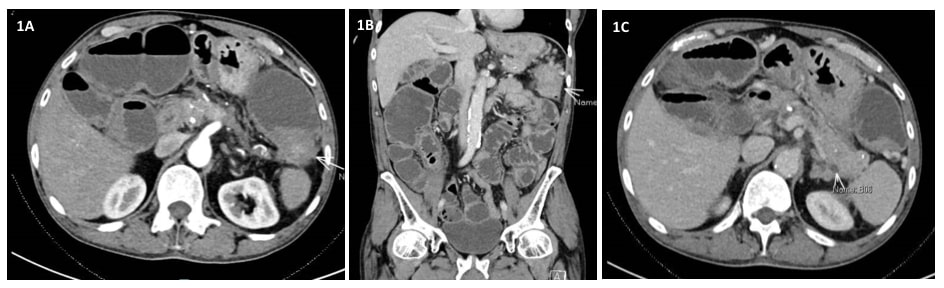

行软式乙状结肠镜检查加内镜下支架置入术(图2)。

腹部和盆腔CT显示脾曲周围有一段环周狭窄伴壁增厚、肠袢近端扩张和慢性胰腺炎特征(图1A-C)。鉴于CEA升高和贫血,初步判断是由脾曲恶性肿瘤引起的肠梗阻。因此对患者行内镜下支架置入术(图2A-B)。但发生了早期支架移位(图3A-C),这种情况非常罕见。因此,患者在内镜下支架置入术后6天行早期腹腔镜下左半结肠切除术,以切除梗阻病变,防止支架移位造成再梗阻。